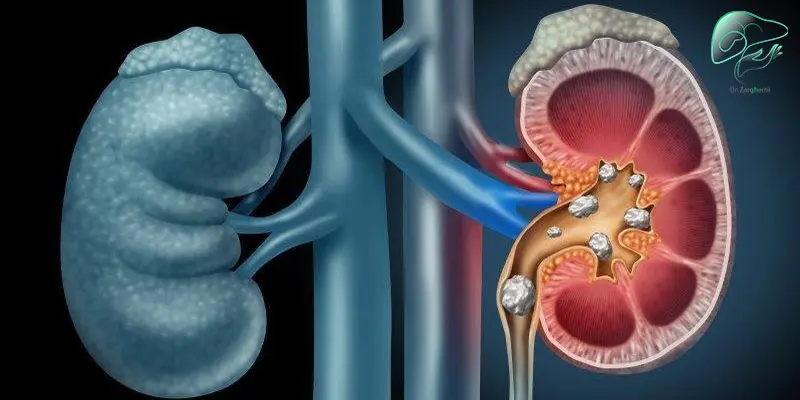

سنگ کلیه چیست؟

به دلایل مختلف بلورهای جامدی از جنس مواد معدنی و نمک در کلیه ایجاد میشوند. به دلیل ساختار خاص این بلورها کریستالی و سخت هستند و لبههای تیزی دارند. با حرکت این توده بلوری به سمت مجاری ادراری آنها را مسدود کرده و ایجاد عوارضی همچون هماچوری (وجود خون در ادرار) میکنند. شیوع این مشکل در مردان بیشتر از زنان دیده میشود ضمنا این بیماری عموما در سنین 20 تا 50 سال بروز میکند.

اگر ادرار دارای غلظت بالایی از مواد معدنی و سایر مواد مانند کلسیم، اگزالات و اسید اوریک باشد، با ترکیب این مواد کریستالهای کوچکی تشکیل میشوند و در نهایت با چسبیدن این کریسالها به هم چندین رسوب سخت یا سنگ ایجاد میشود. اگر در ادرار آب کافی برای جلوگیری از تشکیل کریستال وجود نداشته باشد این بیماری با احتمال بالایی ایجاد میشود.

یک سنگ کلیه ممکن است به کوچکی یک دانه شن باشد و بدون اینکه متوجه شوید آن را دفع کنید. اما اگر سنگ بزرگتر باشد جریان ادرار را مسدود کرده و آسیب زیادی ایجاد میکند. گاهی درد بدتر از زایمان به حساب میآید.